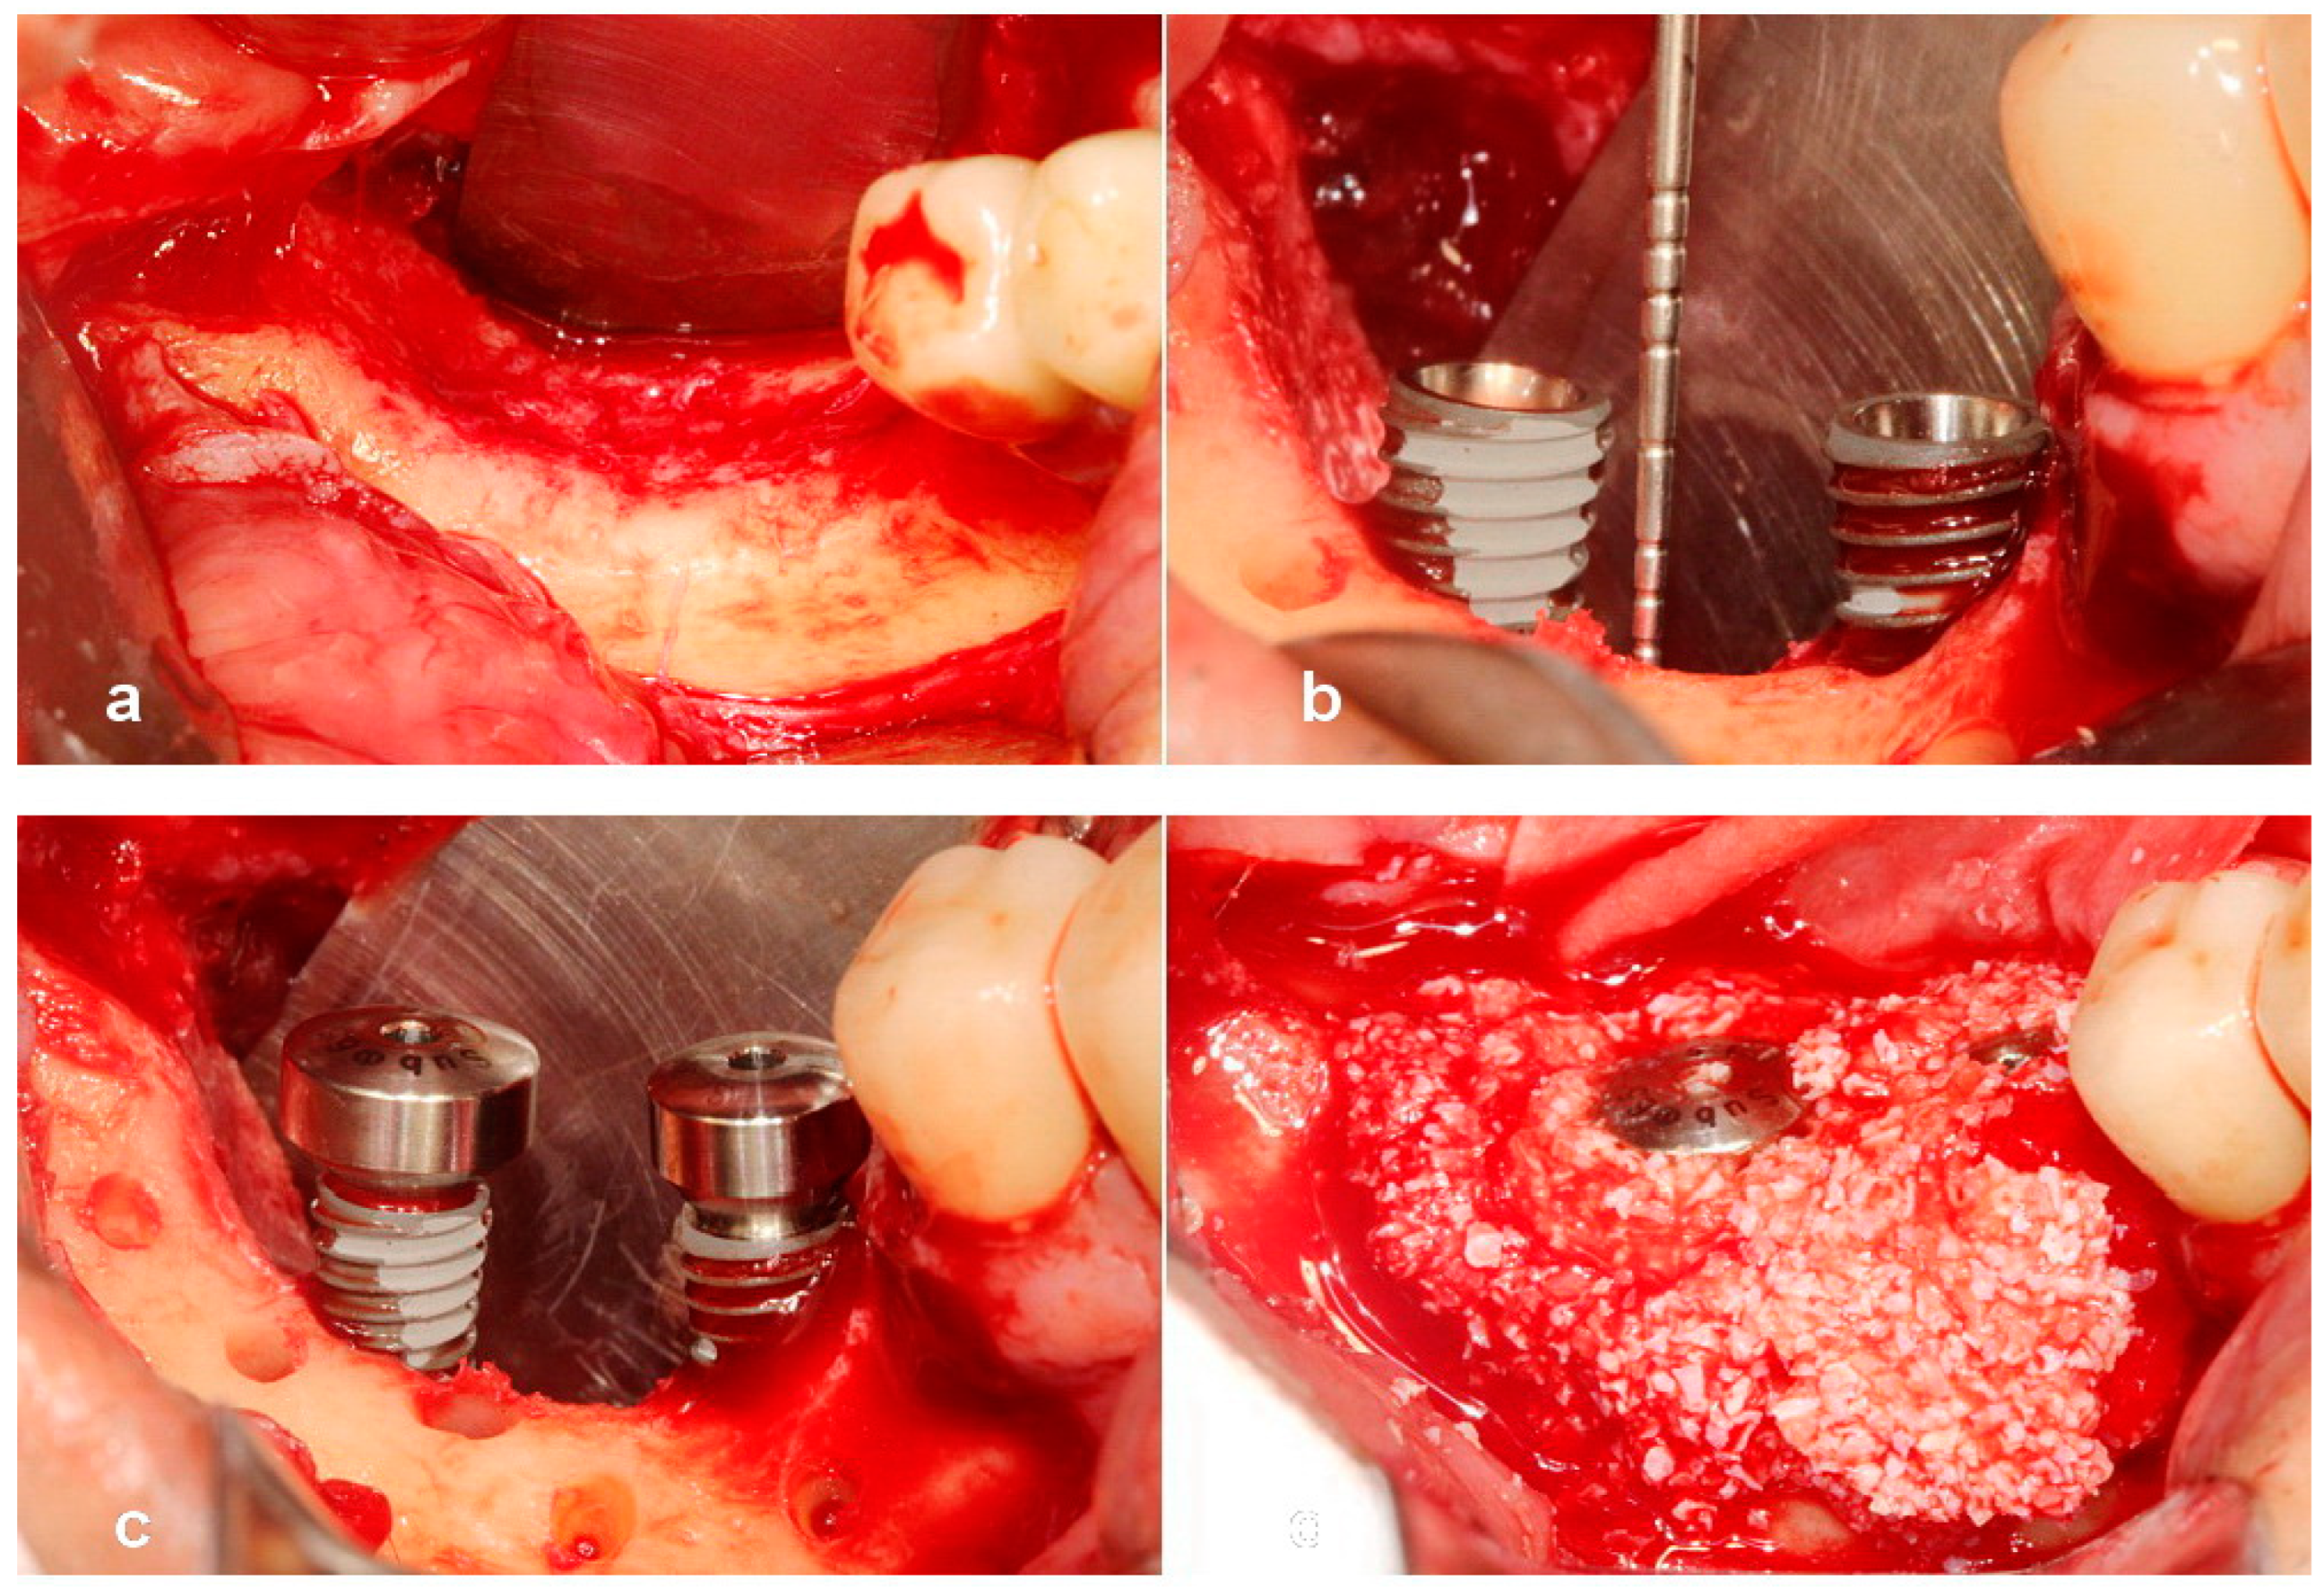

Utilization of Tenting Pole Abutments for the Reconstruction of Severely Resorbed Alveolar Bone: Technical Considerations and Case Series Reports

2. Case Presentations